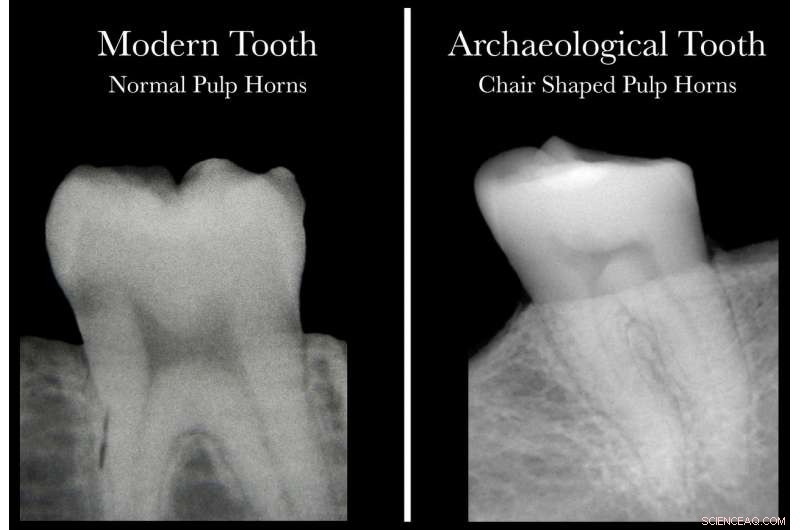

Comparison of dental X-rays from patients with and without VItamin D deficiency. Credit: McMaster University

To avoid wasting precious specimens, the researchers went looking for a way to isolate teeth for further study. By using X-rays to study the readily observable shapes of the "pulp horns"—the dark shadow at the centre of the image of a tooth—they found a consistent, recognizable pattern that could prove helpful not only to their studies of archaeological teeth, but to living people who may not realize they are suffering from Vitamin D deficiency.

The pulp shape in a healthy person's tooth resembles an arch topped by two cat ears, while the pulp shape of a person who has had a severe deficiency of Vitamin D is asymmetrical and constricted, and typically looks like the profile of a hard-backed chair.